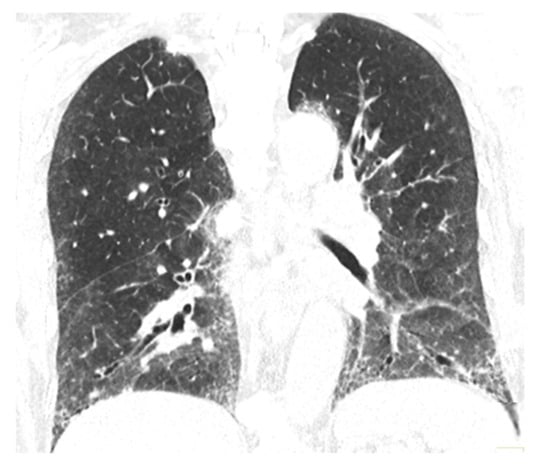

5. Clinical and Paraclinical Presentation